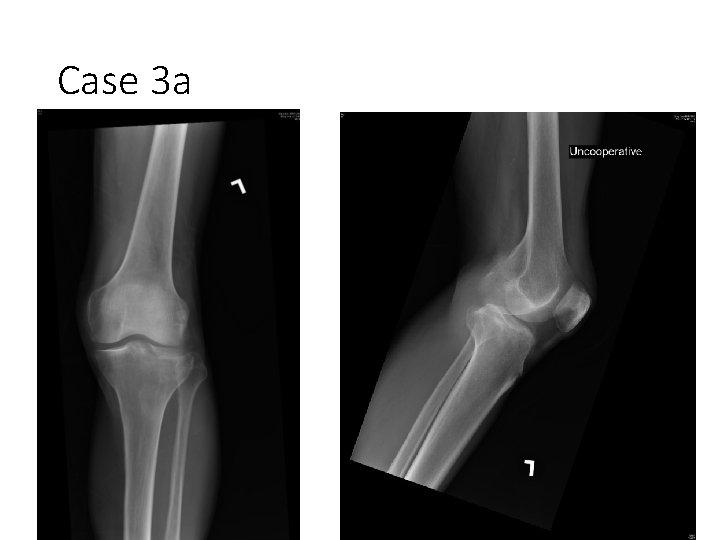

Case 3 a • A 76 man was knocked down by a taxi • He complained of left knee pain 1. What is the X-ray finding? 2. What will you do next?

Case 3 a